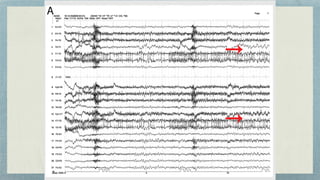

EEG

fi

ndings

In mesial temporal lobe epilepsy, the interictal EEG is

associated with anterior temporal spikes/sharp waves

that are maximum in electrodes T1/F7 or T2/F8 (FT9/

FT10 in the 10/10 system)

Often the spikes can have very focal

elds, and, without the addition of

extra anterior temporal electrodes (T1,

T2), an interictal spike may be missed

The interictal epileptiform

activity is typically

bilateral,even in patients

with unilateral seizures,

but typically one side has a

preponderance

Sleep deprivation can often activate focal epileptiform

discharges; therefore, an EEG with sleep recording is

recommended during the diagnostic workup.

The presence of mid or posterior temporal spikes may

suggest a more widespread epileptogenic network

even in the presence of clear mesial temporal

pathology

The ictal EEG is typically characterized by rhythmic

alpha or theta activity that evolves into higher-

amplitude rhythmic delta or theta activity that may be

sharply contoured or contain discrete spikes

Often, the initial ictal discharge may be preceded

by an initial sharp wave or suppression of the

normal EEG patterns or epileptiform activity

that was occurring immediately before the ictus